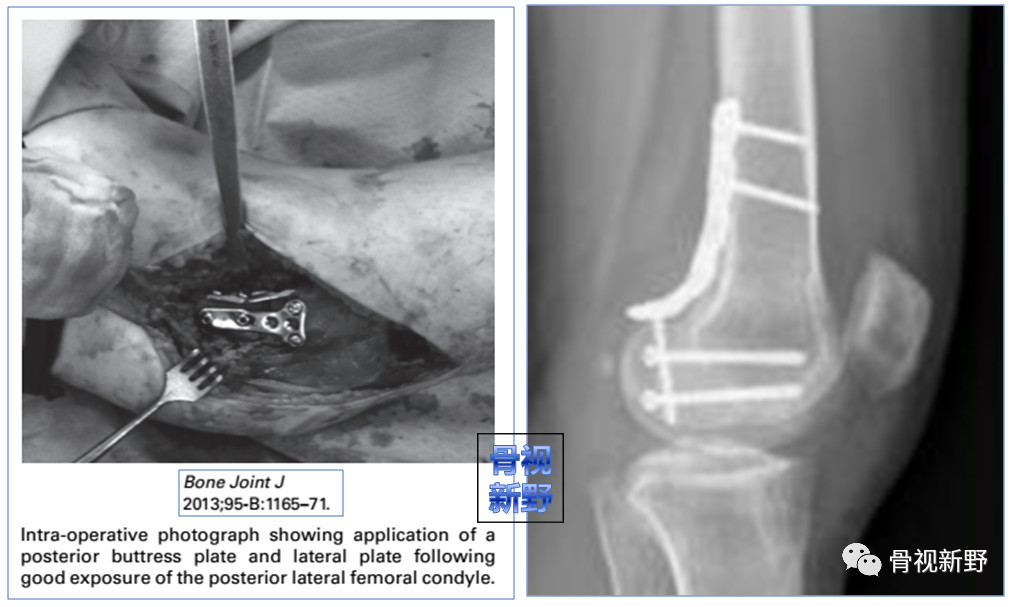

Buttress理念:由于Hoffa骨折垂直剪力较大,单纯拉力钉固定易致骨折移位、畸形愈合或不愈合。

因此,使用防滑、支撑的Buttress钢板以对抗垂直剪力有一定的必要性。

后外侧入路

适应症:II型外侧髁Hoffa骨折。操作:自髂胫束和股二头肌之间进入。

改良后外侧入路

适应症:II型外侧髁Hoffa骨折。

操作:自股骨外上髁至腓骨颈做一纵向切口,首先在腓骨颈远侧显露腓总神经,并向近侧游离,切开股二头肌肌腱(前)和腓总神经之间的深筋膜,股二头肌牵向外侧,腓总神经牵向内侧,显露后外侧关节囊,自远侧半月板附着部位向近侧纵向切开关节囊,在半月板位置的关节囊留置缝线,用以牵开关节囊显露股骨远端。